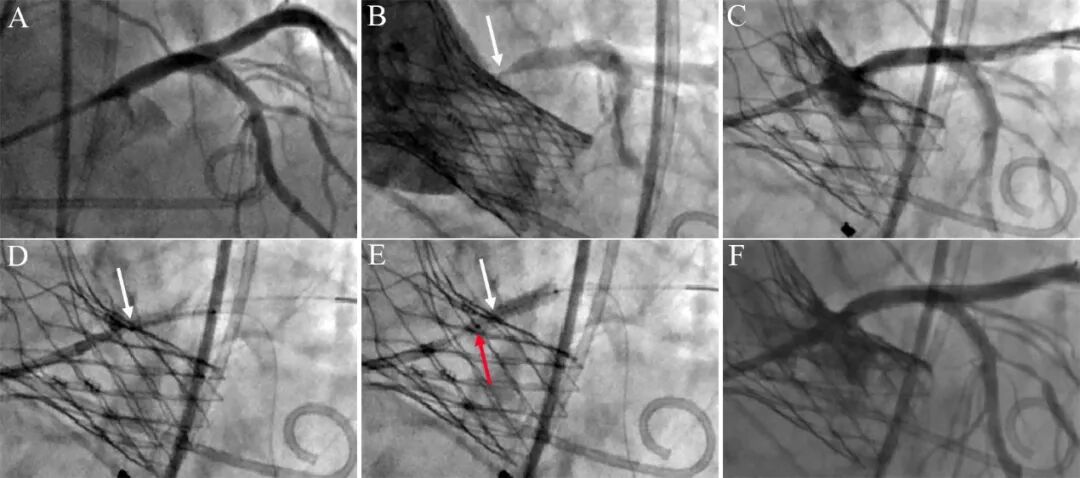

图4 张力性移位(TAVR后支架植入)。TAVR术前左主干正常(A),TAVR术中损伤左主干开口(B),需要紧急置入冠脉支架。预扩张后,左主干开口呈喇叭状(C)。3.5*13mm冠脉支架穿过TAVR梁送至左主干中远段,然后回撤到位,冠脉支架标志点齐平主动脉TAVR梁(D,白色箭头为支架预定位标志点)。冠脉支架释放瞬间,支架向主动脉内跳跃移位2mm(E,白色箭头为预定位时的支架标志点,红色箭头为实际释放时的标志点)。尽管造影结果良好(F),但支架突出主动脉略多,不利于下次复查造影。事后分析成因:定位时,支架回撤张力并未得到释放,但与TAVR梁阻力达成平衡;支架球囊扩张时,TAVR梁受挤压,阻力骤降,支架在回撤张力作用下向近端跳跃滑动。